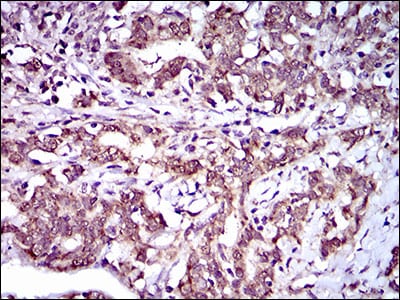

- Immunohistochemical analysis of paraffin-embedded human cervical cancer tissues using ABCG5 mouse mAb with DAB staining.